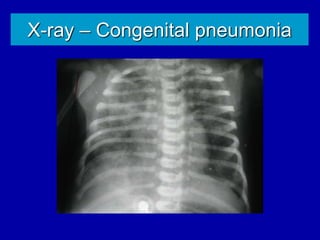

X-ray – Congenital pneumonia